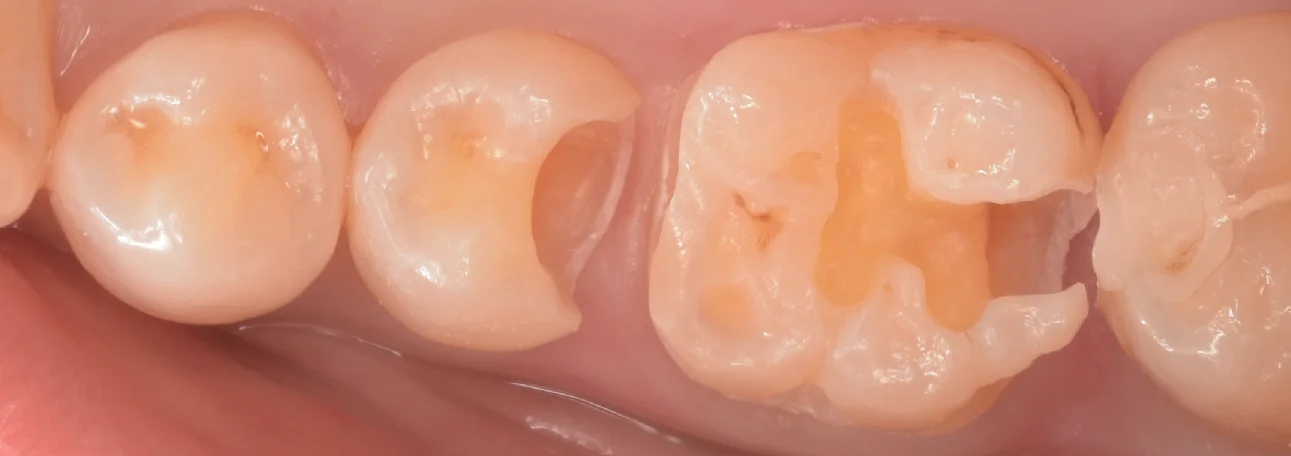

古い詰め物を除去し、虫歯が見やすくなったのがこちらです。

ところどころ茶色いのがあるのがわかると思います。

実は虫歯とは黒いものだけではありません。

白っぽい色の方が進行が早いんですね。

なので、取り切ってみると・・・